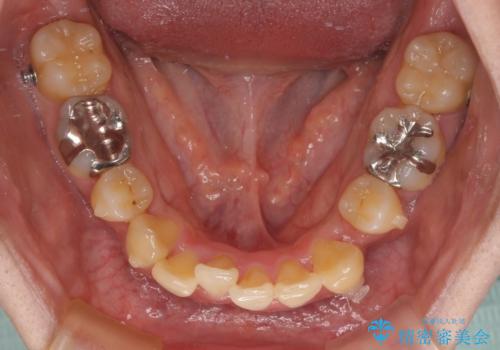

- 1年8ヶ月

- 5-10回

ワイヤー矯正と比較すると、八重歯が後方に傾斜した仕上がりとなりましたが、患者様ご希望のインビザラインにて十分な歯列を達成することができました。